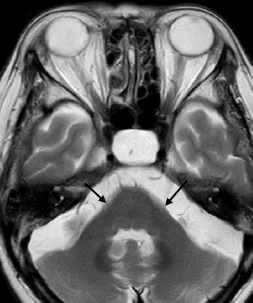

- A pattern of prominent atrophy involving the medulla oblongata and cervical spinal cord with sparing of the lower pons (ie, “tadpole sign”)8,53

An additional imaging pattern characterized by bilateral symmetric hyperintensity on T2-weighted imaging involving the central inferior olivary nucleus, the pyramids, and the cuneate and gracile fascicles, with sparing of the peripheral inferior olivary nucleus and inferior peduncle (termed the “chipmunk sign”), is a common feature in people with Alexander disease regardless of age of onset.62